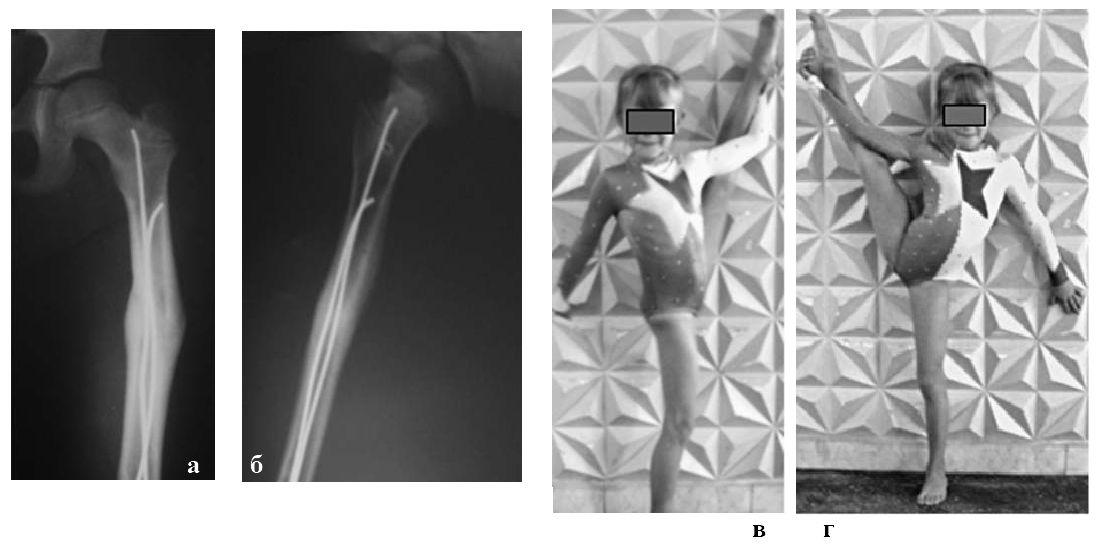

Второй клинический пример, Больная К., 7 лет. Диагноз: закрытый «бамперный» перелом диафиза бедренной кости с полным смещением отломков. (Рис. 3-5)

Наличие интерпозиции мягких тканей стало показанием для открытого остеосинтеза облегченным аппаратом Илизарова с интрамедуллярным армированием спицами с биоактивным ГА покрытием. Первые признаки репаративной регенерации кости на рентгенограммах бедра появились через 3 недели и на 25 день фиксации аппарат Илизарова был демонтирован. Через 1,5 месяца девочка уже приступила к регулярным тренировкам художественной гимнастики.

Рис. 3. Рентгенограммы бедра пациентки К.,7 лет:

а - до операции;

б, в - в день остеосинтеза;

г - через 21 день после операции.

Рис. 4. Пациентка К., через 3 месяца - фотографии (а, б) и рентгенограммы бедра (в).

Рис. 5. Рентгенограммы бедра (а, б) пациентки К. и ее функциональные возможности (в, г) через 6 Месяцев после демонтажа аппарата Илизарова.